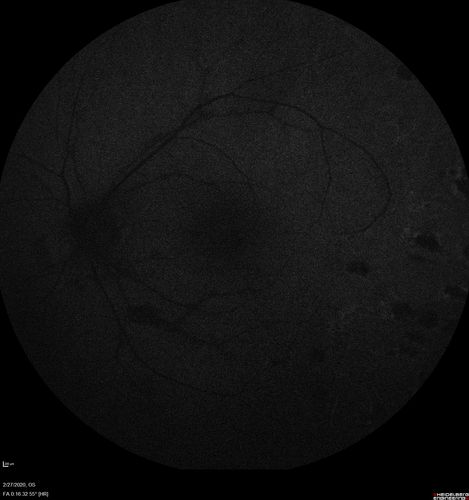

Eales Disease and fresh vitreous hemorrhage - 20 year old man

20 year old mane with fresh vitreous hemorrhage in the right eye.  At age 15 he had a PPV and laser in the left eye and laser in the right eye.  The vision is OD 20/80 PH 20/25, OS 20/25.  The left eye has a mild cataract.  He had prior testing for coagulopathies which was negative.  Testing done for syphillis and TB was negative.  Additional laser was done to prevent further bleeding in the right eye.